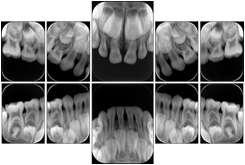

5 Standard + Occlusal Maxilla A Dental Image Layout

DL-C008A

Reference: DL-C008-U1L0

Reference: DL-C008-U2L0

5 Standard + 3 Occlusal Mandible A Dental Image Layout

DL-C009A

Reference: DL-C009-U0L1

Reference: DL-C009-U0L2

7 Standard + 3 Occlusal Maxilla A Dental Image Layout

DL-C010A

Reference: DL-C010A-U1L0

Reference: DL-C010A-U2L0

7 Standard + 3 Occlusal Mandible A Dental Image Layout

DL-C011A

Reference: DL-C011A-U0L1

Reference: DL-C011A-U0L2